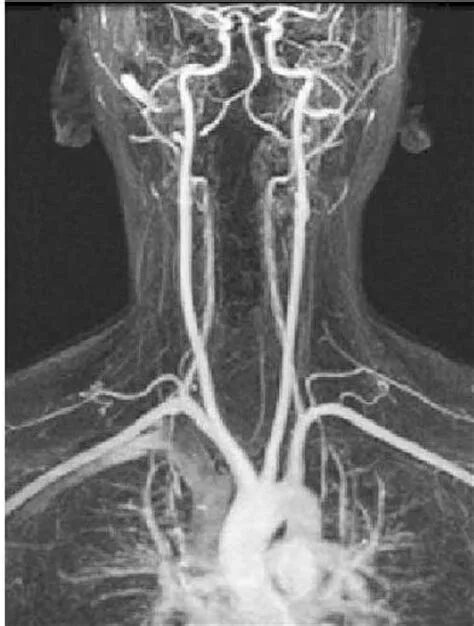

Гипоплазия сегмента v4 позвоночных артерий